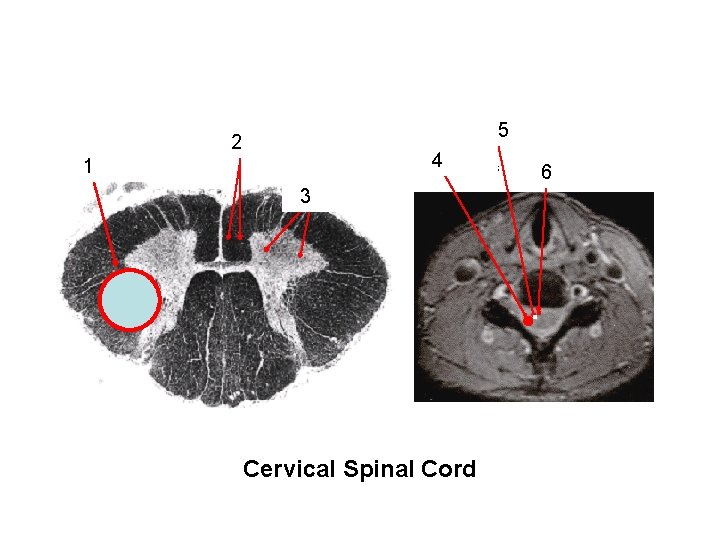

Position of: ventral horn corticospinal, vestibulospinal, with LMN & reticulospinal tracts lateral corticospinal tract medial & lateral & rubrospinal tracts ventral corticospinal, vestibulo+ rubrospinal tract motor nuclei in spinal, & reticulospinal tracts 5 2 4 1 6 3 ventral horn . . Cervical Spinal Cord